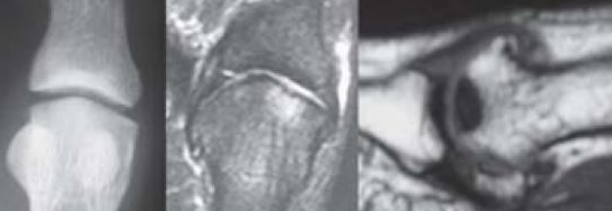

• Na avaliação radiológica, qual a indicação para realização de ressonância?

A

• Suspeita de lesão condral